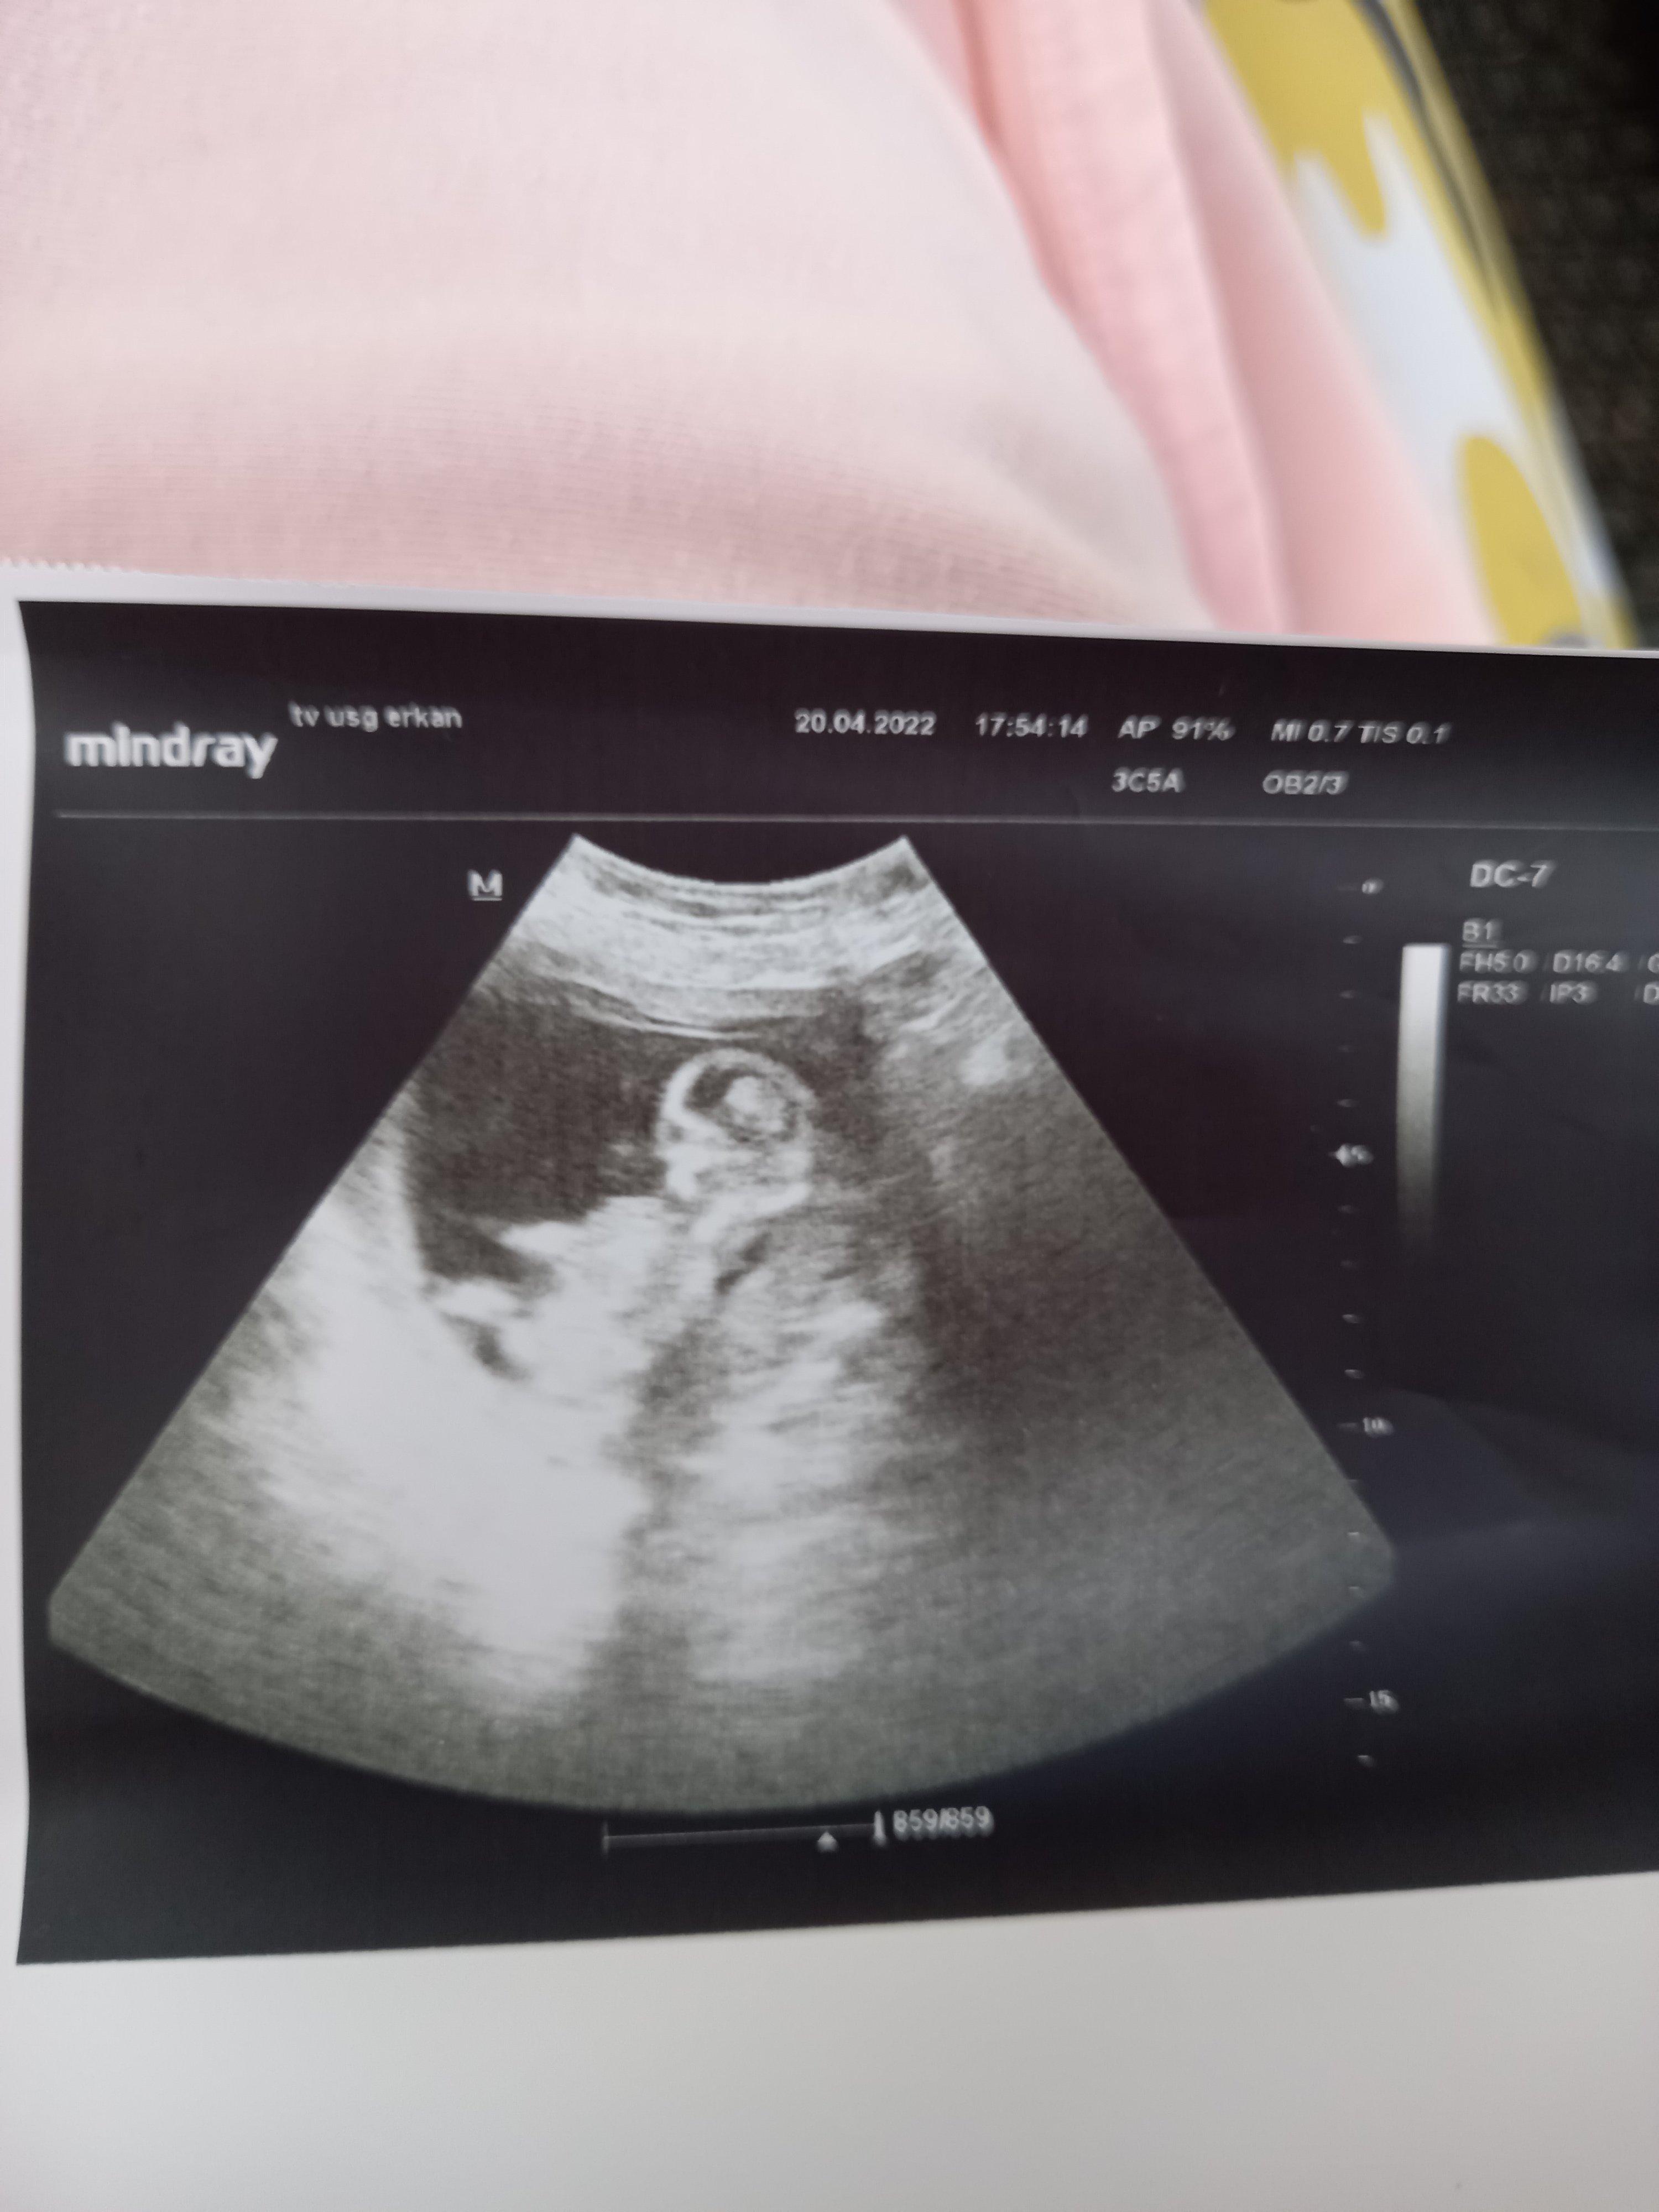

Sorum var 14 haftalık cinsiyet tahmini yapabilen var mı

Konu Başlığı 14 haftalık cinsiyet tahmini yapabilen var mı

Onu görmek için erken mi acaba ya doktor bile bişey demedi 13 haftalıkti 15-16 da net olarak söyliyim dedi